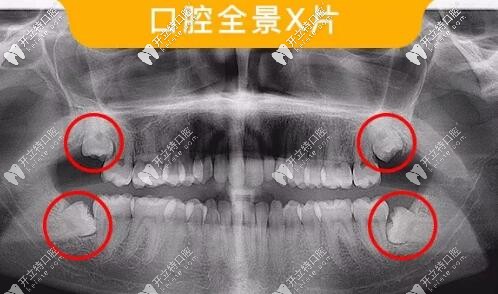

智齒口腔全景片

此類智齒需要拔除

如圖所示這樣沒有正常萌出,傾斜、阻生的智齒,容易造成食物鑲嵌堵塞,容易齲壞需要盡早拔除。